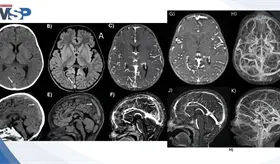

Un reciente estudio ha revelado que las características vasculares de la retina, que se pueden observar mediante fotografía de fondo ocular, están estrechamente asociadas con el riesgo de sufrir un accidente cerebrovascular.